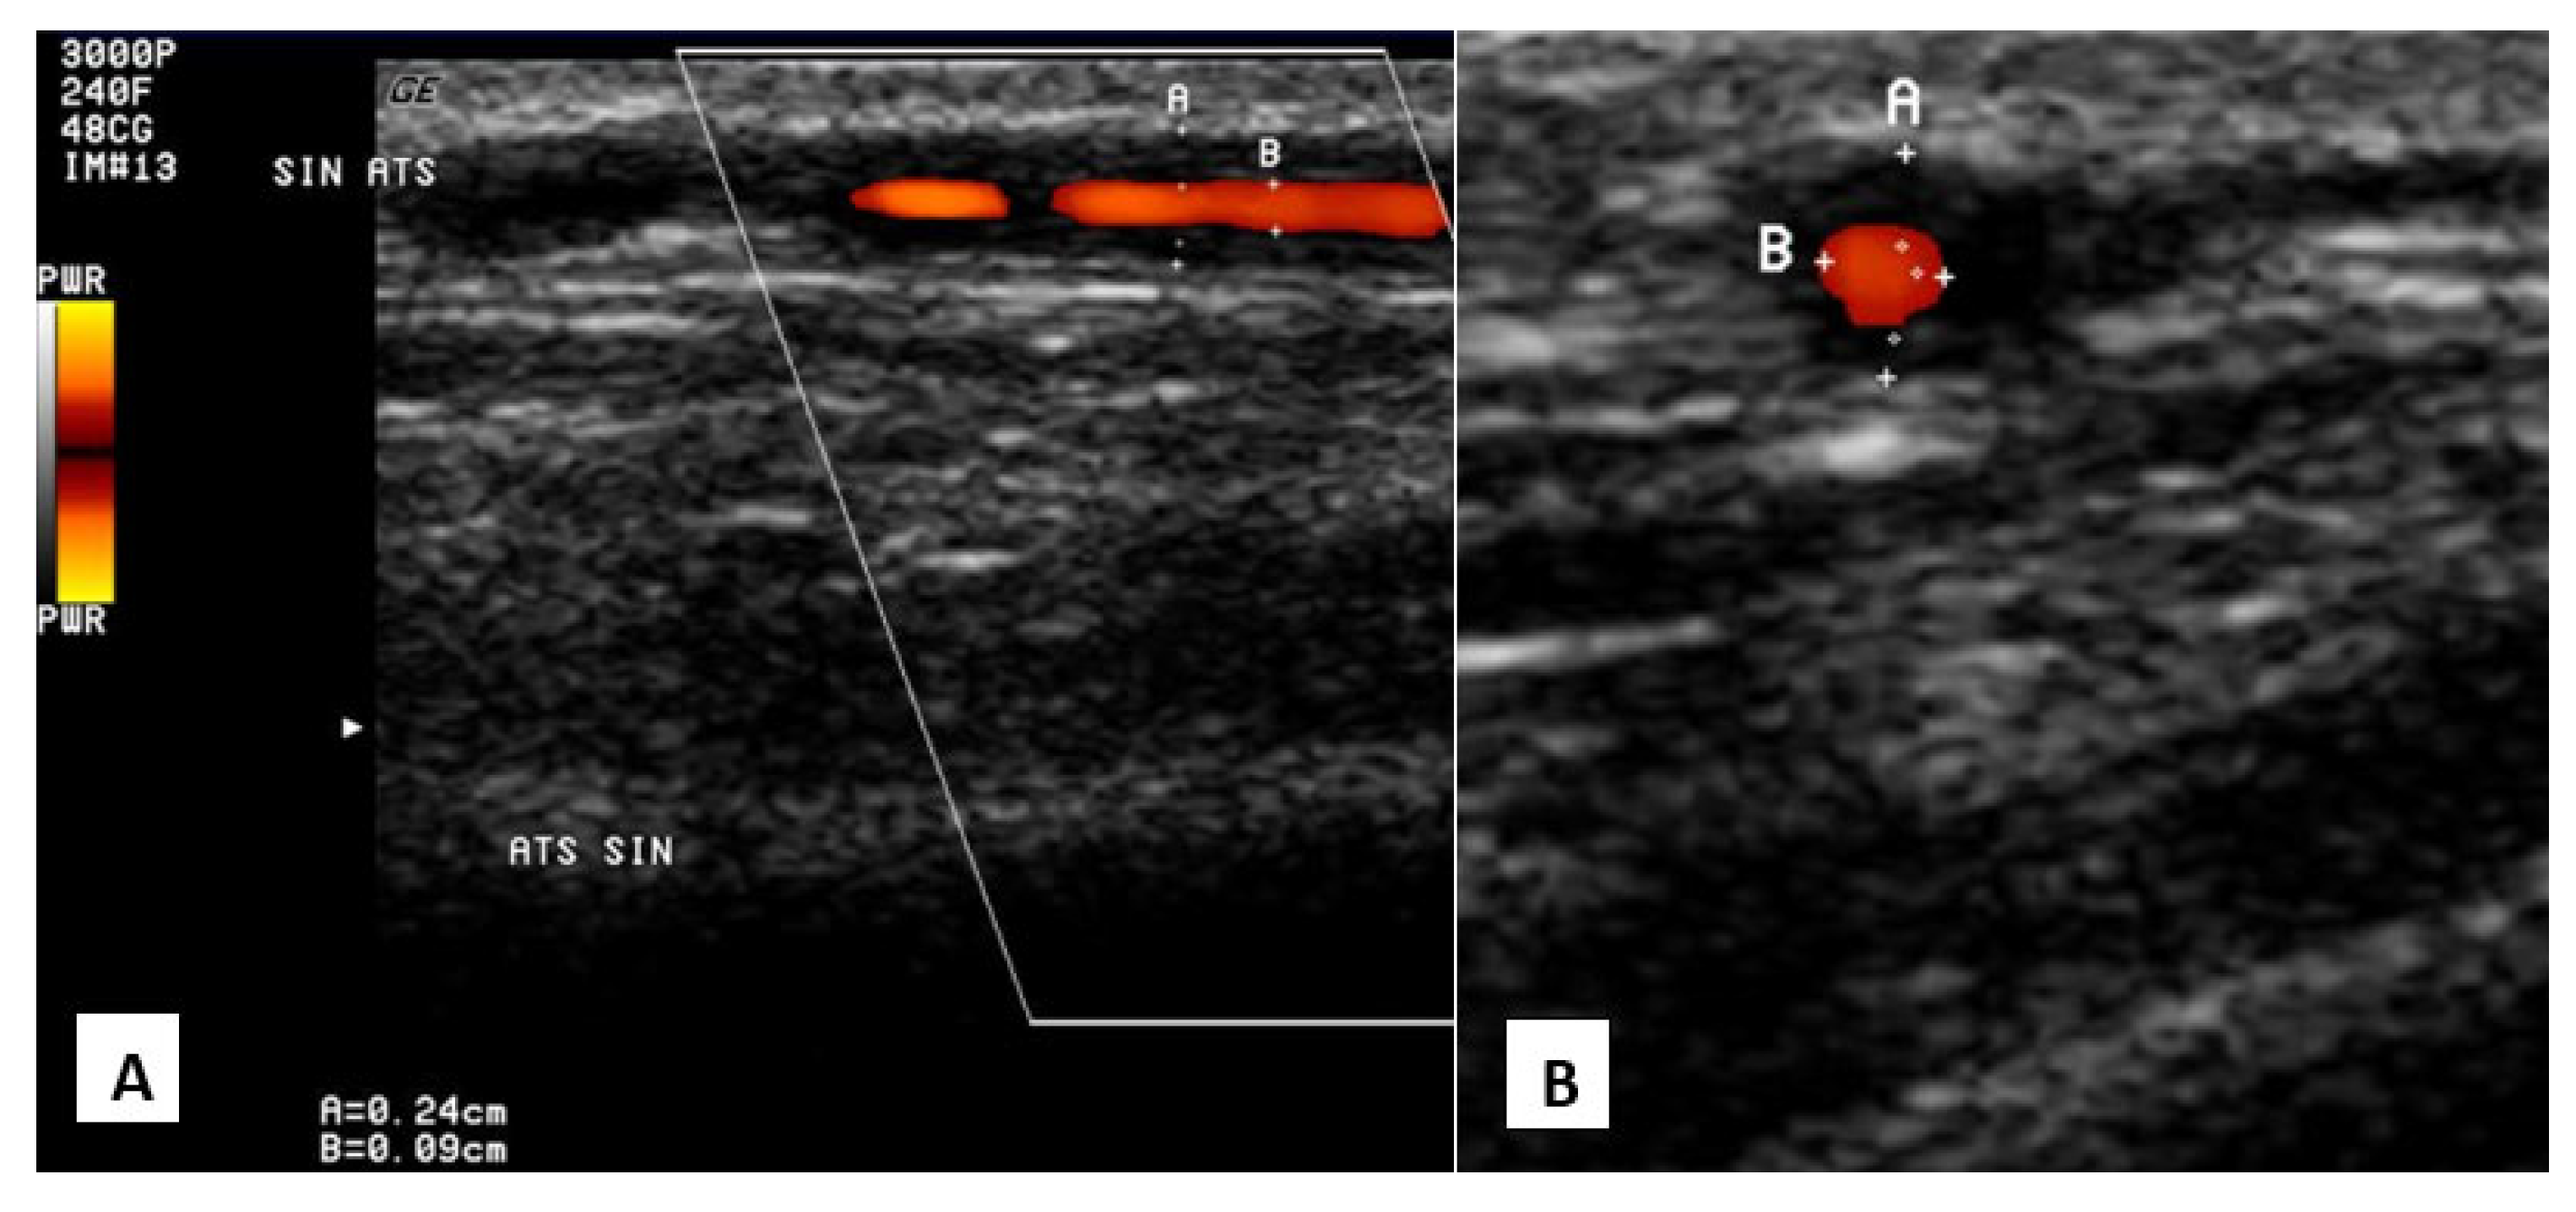

4.1.1. Giant Cell Arteritis